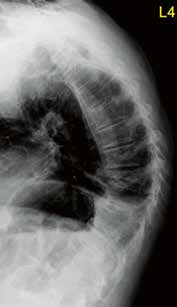

Es ist im Wesentlichen zwei Arbeitsgruppen zu verdanken, dass für bestimmte Aktivorthesen bzw. Aktivmieder Evidenz für ihren Einsatz bei Frauen mit postmenopausaler Osteoporose vorliegt (Abb. 2). So konnten Pfeifer et al. 32 in einer prospektiven randomisierten Crossover-Studie zeigen, dass das Tragen einer Orthese im Sinne einer Aktivorthese aus einer kalt verformbaren beweglichen und schwingenden Rückenpelotte mit einem Gurtsystem, welches einen individuell anpassbaren Formsitz erlaubt, über 6 Monate für täglich zwei Stunden zu einer Verbesserung verschiedener relevanter Parameter führt. So konnte im Vergleich zur Kontrollgruppe eine Verbesserung der Rumpfmuskelkraft, der Körperhaltung und der Lebensqualität bei über 60-jährigen Frauen mit Osteoporose und mindestens einer osteoporotischen Wirbelkörperfraktur nachgewiesen werden. Weiterhin wurden eine Abnahme des Kyphosewinkels und damit eine Verbesserung der Haltung und eine Schmerzreduktion im Vergleich nachgewiesen. Nach erfolgter Behandlung hielten diese Effekte für weitere 6 Monate an. Der Effekt wird erklärt mit einer Aktivierung der Muskulatur im Sinne eines Biofeedback-Mechanismus über die zugelastischen Materialien.